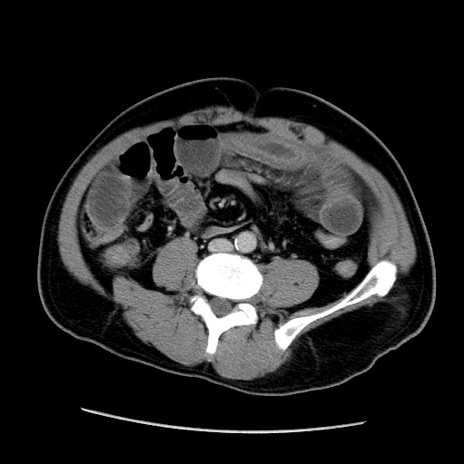

症例22(横断像)

【症例】50歳代男性

【主訴】腹痛

【現病歴】AVMからの被殻出血のため回復期リハ病棟入院中。 本日午後3時頃急に下腹部痛が出現した。

【既往歴】AVM、被殻出血、虫垂炎、高血圧

【身体所見】意識晴明、左半身不全麻痺、会話の理解は良好、36.5°C、腹部:膨隆、全体に板状硬、下腹部正中に圧痛点あり、反跳痛-、筋性防御不明、右下腹部にope scar

【データ】WBC 9400、CRP 0.06